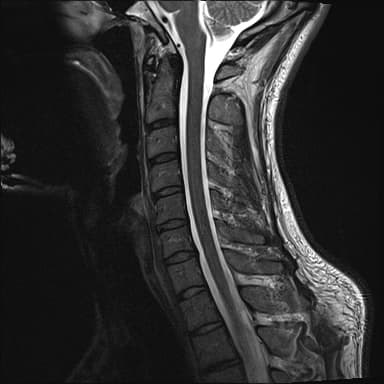

Discover the cause of your neck pain with Cervical MRI! Fast and reliable MRI imaging service with expert radiologists. Click for medical imaging center advantages!